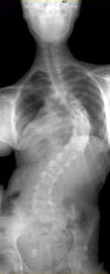

spine x-ray before treatment spine x-ray after treatment